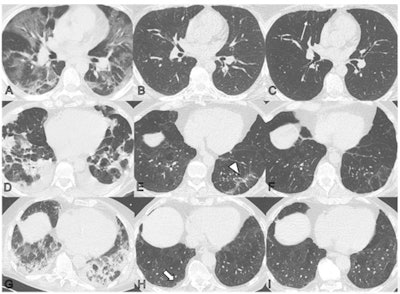

Serial noncontrast axial chest CT exams of three study participants with prior COVID-19 pneumonia. Chest CT of a 44-year-old man (upper row, A-C) displayed extensive bilateral ground-glass opacities (GGO) and supleural reticulation during acute COVID-19 (A). At the two-month follow-up almost complete resolution of GGO with residual subpleural reticulation in the middle lobe was noted (B). These subpleural reticulations (arrow) persisted up to one year after onset (C). Chest CT of a 68-year-old-man (middle row, D-F) demonstrated patchy bilateral consolidations, a subpleural arcade-like sign, and pleural effusions during active infection (D). At the two-month follow-up, a substantial improvement of organizing pneumonia pattern was noted with GGO and subpleural reticulation including arcade-like sign (arrowhead) in the left lower lobe (E). At the one-year follow-up, further improvement was noticed. However, subtle reticulation and GGO could still be detected (F). Chest CT of a 79-year-old man (lower row, G-I) displayed bilateral consolidations and small areas of GGO while admitted to the intensive care unit (G). At the two-month follow-up, residual GGO and small subpleural microcystic changes (thick arrow) were noticed (H), which persisted up to one year after onset (I). Images and caption courtesy of the RSNA.Luger's group conducted a study that included 91 patients evaluated with chest CT after contracting COVID-19 pneumonia at two, three, six, and 12 months after symptom onset. Of these, 49 (54%) showed abnormalities on chest CT at the one-year mark. CT exam findings were graded by lung lobe using a severity score that ranged from 0 (normal) to 25 (all lobes involved).

- Common abnormal findings were subtle subpleural reticulation, ground-glass opacities, or both (34%); 20% of the abnormal CT exams showed extensive ground-glass opacities, reticulations, bronchial dilation, or microcystic changes.

- Men older than 60 were particularly vulnerable to showing persistent lung abnormalities on CT at one year after symptom onset.